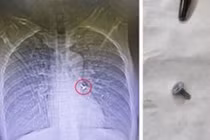

Bàn chải đánh răng trong dạ dày bệnh nhân- Ảnh BVCC

Tuy nhiên, bằng trình độ chuyên môn kinh nghiệm và sự tận tâm vì người bệnh sau khoảng thời gian làm việc khẩn trương, cố gắng, ekip nội soi do ThS.BS Lê Mạnh Hùng làm trưởng kíp đã thành công gắp được dị vật là 1 chiếc bàn chải đánh răng nguyên chiếc dài thân phình vị đến hang vị dạ dày, dị vật dài khoảng 20cm.

Chiếc bàn chái đánh răng được các bác sĩ lấy ra - Ảnh BVCC